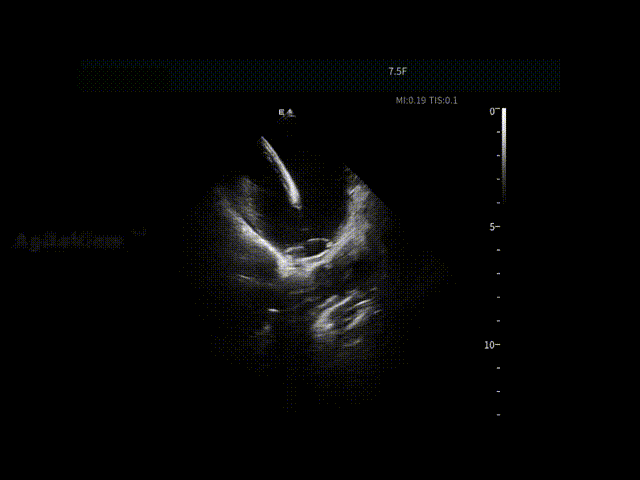

ICE实时超声影像帮助术者直观评估左心耳内是否存在血栓,并同步观察心包状态,为手术是否继续推进提供重要影像依据,使后续操作建立在"可视,可判断"的安全基础之上。

LAA血栓筛查

术前心包-有明显积液